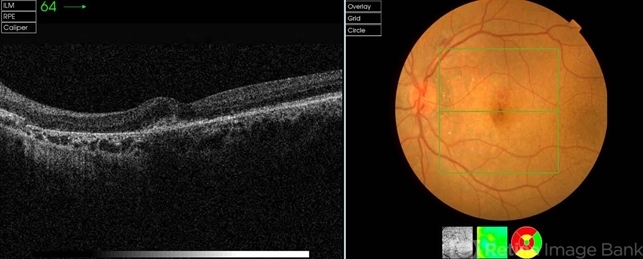

- pseudoxanthoma elasticum (PXE), angioid streaks, choroidal neovascularization (CNV), optical coherence tomography (OCT)

- Hamid Ahmadieh, MD, Ophthalmic Research Center, Labbafinejad Medical Center, Shahid Beheshti University of Medical Sciences

Optical coherence tomography system

Topcon - Description

- Color fundus photograph and OCT image of a 35-year-old woman with juxtafoveal CNV due to angioid streaks of choroid secondary to PXE.